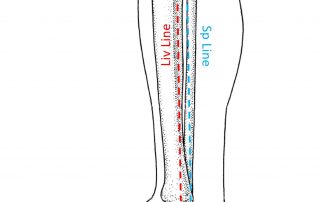

תלונה על כאבי גב תחתון היא נפוצה מאוד בקליניקה. לרוב, הכאב ממוקם לרוחב "חגורה" - כלומר משני צדי הגב; במרכז אבל "רחב" (מטופל מניח את כף היד על האיזור הכואב); או בצד אחד (גם אם המטופל אינו מודע לזה, בהרבה מקרים בהם הוא מתלונן על כאב גב מרכזי - הוא בעצם דומיננטי יותר בצד [...]